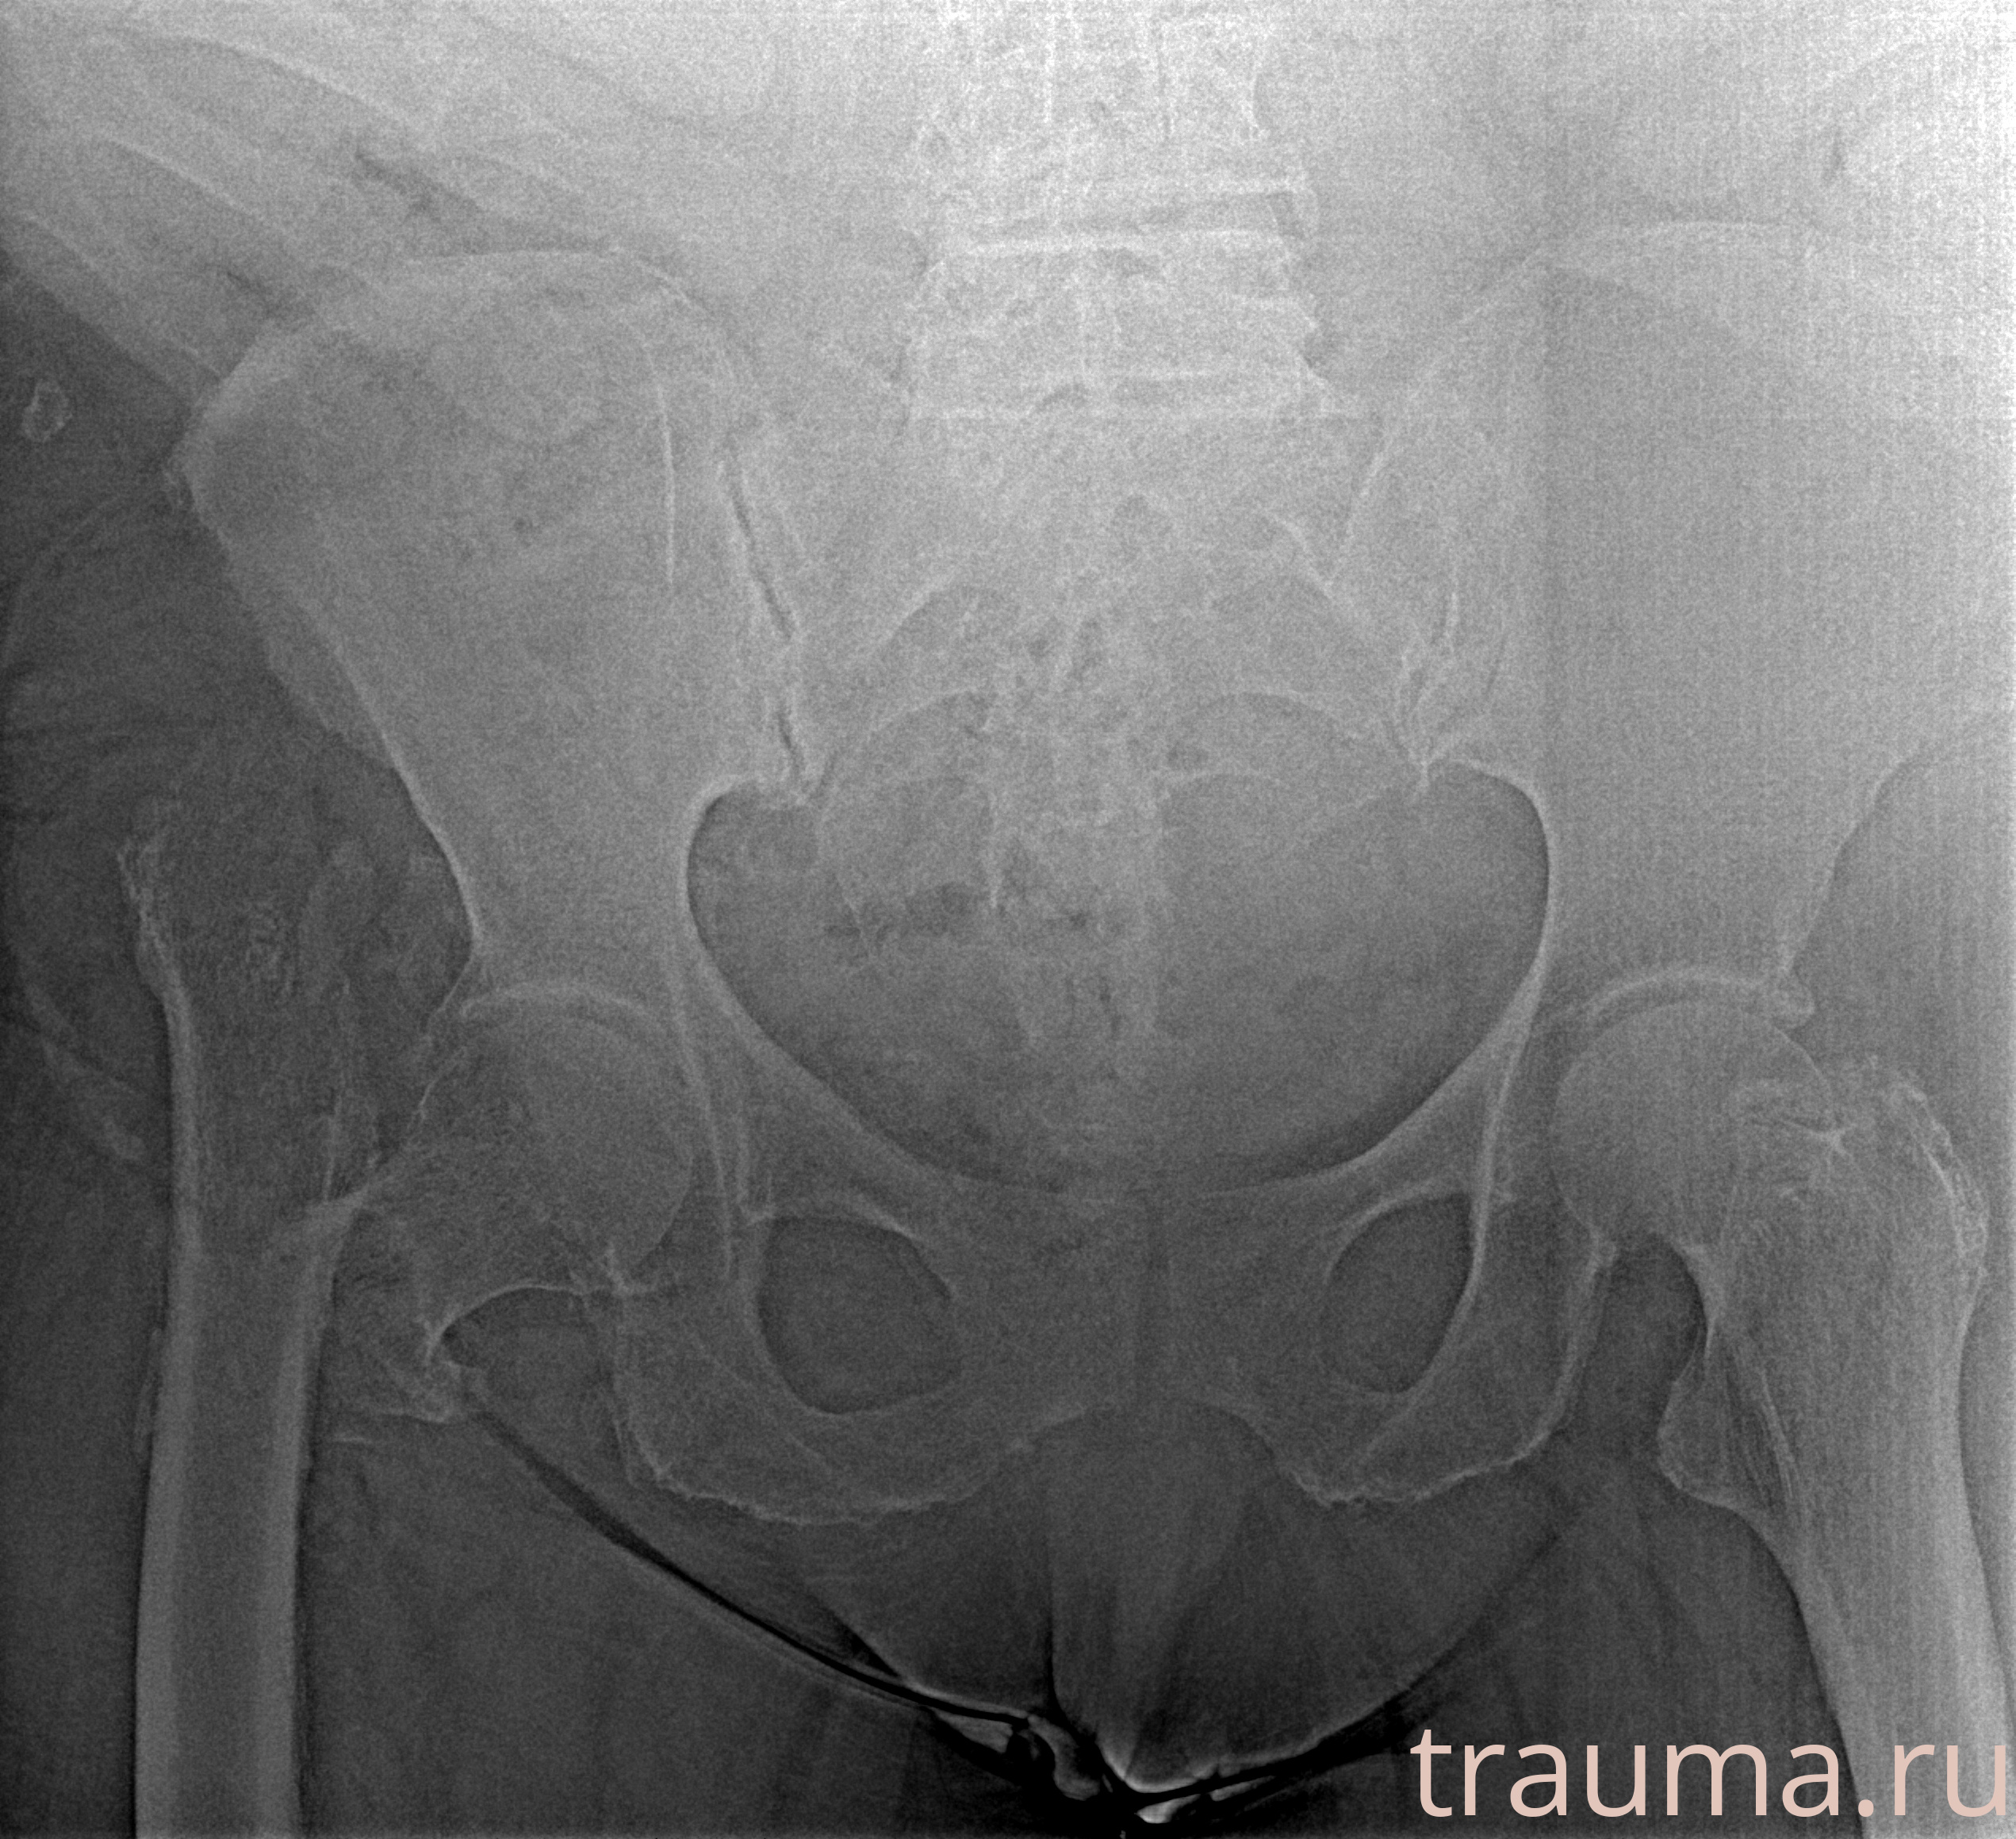

Рентгенограммы

Рентген на дому: по вашему адресу приезжает врач-рентгенолог, травматолог-ортопед с мобильным рентгеновским аппаратом, проводит диагностику травмы или заболевания, делает необходимые рентгенограммы, дает рекомендации по дальнейшему лечению. Получить качественные снимки в домашних условиях возможно благодаря уникальной методике, разработанной МосРентген Центром для института  Склифосовского

Яркость: 1   Контраст: 1   Инвертировать: 0 Увеличение: 1

Перетаскивайте мышь вверх/вниз для контраста, влево/право для яркости. Прокрутка колесом изменяет масштаб. Нажмите Сбросить для возврата к исходному изображению. При увеличении держите мышь в той области, которую хотите рассмотреть.